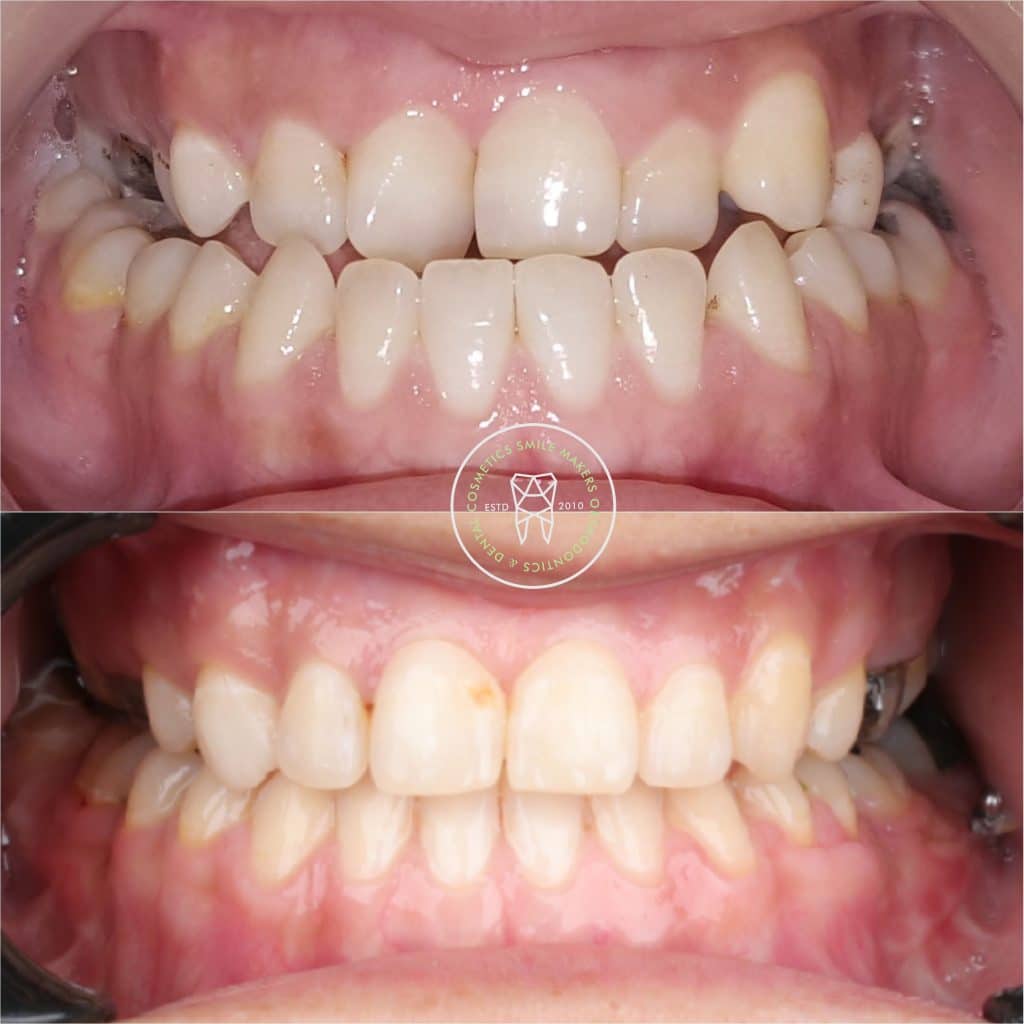

*Intraoral : incisors cl III complicated with sever crowding in upper arch , extracted UR3 , LR and LL 6s , anterior and posterior crossbite , upper midlineshift to the right , multiple restorations and fair OH

* complication : the case dismissed after surgery without instructions to keep using the wafer along with elastics , also multiple debondings happened during the surgery , so patient came to me 3 weeks after surgery with posterior openbite , progressing shift of lower midline towards the right side , and cl III canines in left side

*managment : intermaxillary elastics , and unilateral buccal shelf TAD inserted in left side to distalize this segment to obtain cl I canine , and coincident midline .